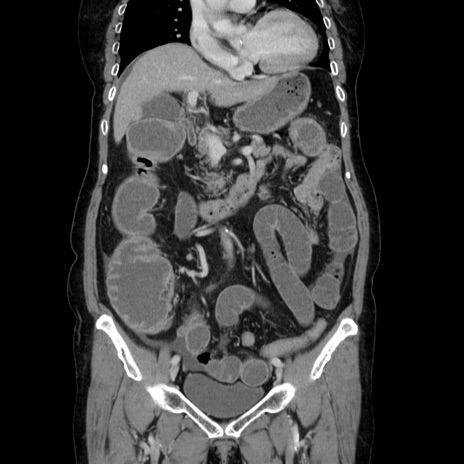

横断像

【症例】70歳代女性

【主訴】お腹が張る

【現病歴】1週間くらい前から腹部膨満の自覚あり。昨日夜から増悪したため、本日救急外来受診。

【身体所見】意識清明、BT 36.5℃、BP 165/106mmHg、HR 80bpm、SpO2 98%、腹部:膨満、軟、自発痛・圧痛なし、触診にて不快感あり、腸蠕動音:減弱

【データ】WBC 12600、CRP 1.04